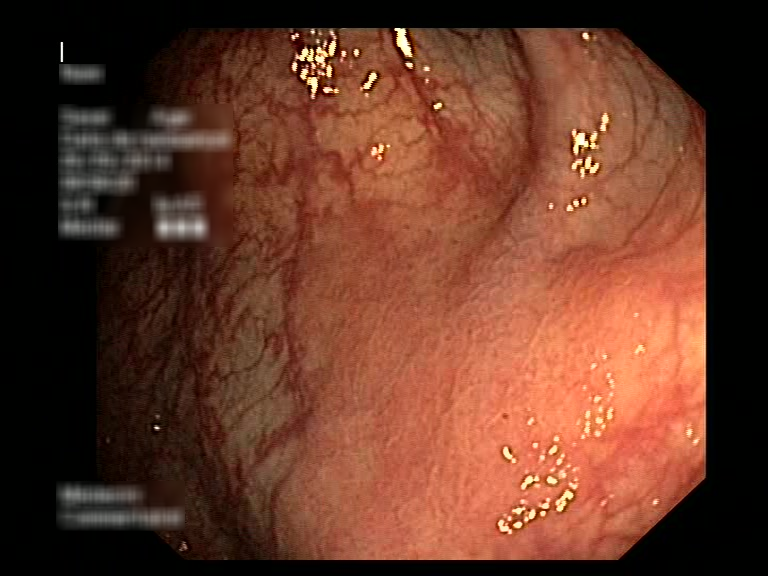

| Lesion | White Light Frame | NBI Frame | White Light Video | NBI Video | Camera Calibration |

| serrated_01 |  |

|

WL.mp4 | NBI.mp4 | cam.xml |